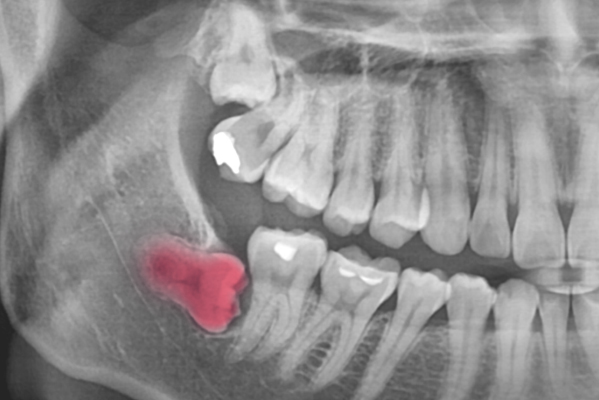

사랑니가 정상적으로 나오지 않고 비정상적인 형태로

나면 참기 힘들 정도의 통증을 동반하는 경우가 많습니다.

이런 경우에는 통증을 줄이기 위하여 사랑니 발치를 진행해야 합니다.

대학병원에서 주로 사용하는 3D CBCT 스캔은 사랑니의 형태, 뿌리 구조는

물론 하치조 신경관의 거리까지 기존 디지털 기기에 비해 3000배 이상

정밀하게 촬영하여 보다 안전한 시술 계획 수립이 가능하게 해줍니다.